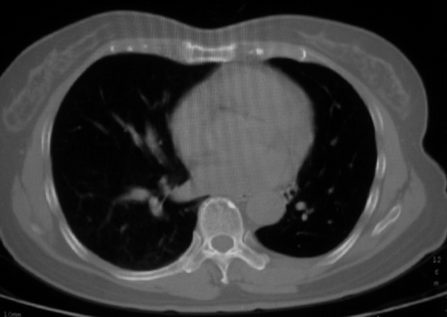

以下是引用李衡钧在2008-7-24 14:24:00的发言:[br]左侧胸廓变小,左肺上叶见大面积致密阴影,其内有空洞及不规则钙化。上纵隔略向左移位,上肺胸膜增厚。左肺门及纵隔淋巴结增大。右肺见散在的致密结节影。[br]印象:继发性肺结核。